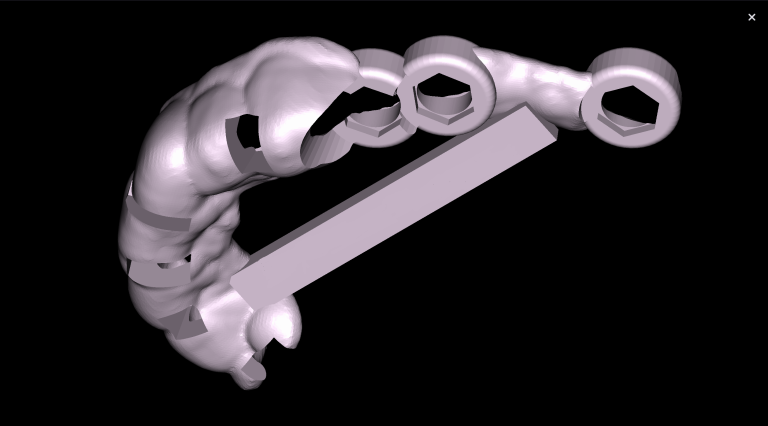

Combining DICOM data and intraoral scans in Diagnocat STL module allows for the creation of 3D models

Based on these data, stereolithographic models were created and a surgical template for gingivectomy was planned

The future gum contour was determined using diagnostic wax-up